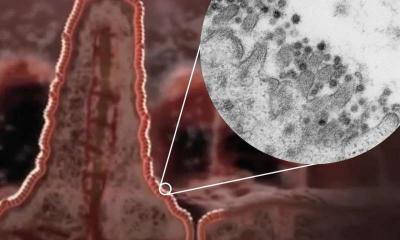

स्कॉटलँड स्कूल ऑफ लाईफ सायन्सनी कोरोना व्हायरसच्या काही प्रिंट्स फोटो दाखवले आहेत. त्यात असं दिसून येत आहे कोरोना व्हायरसचं आतड्यांवर फक्त संक्रमण होत नसून कोरोना आतड्यांमध्ये वेगाने पसरत जातो.

माणसाच्या शरीराला संक्रमित करून आतड्यांपर्यंत पोहोचत असलेला कोरोना व्हायरस पांढऱ्या रंगाचा दिसतो. कोरोनाचे निरक्षण करण्यासाठी शास्त्रज्ञांनी अल्ट्रा पॉवरफुल मायक्रोस्कोपचा वापर केला.

शरीरातील कोरोना व्हायरसची माहिती देणारे हे फोटो ३० ते ५० गीगाबाईट्सचे आहेत. स्कूल ऑफ लाईफ सायन्सचे क्वारंटाईन सेल बायोलॉजी प्रोफेसर यांनी सांगितले की, कोरोना व्हायरस आतड्यांपर्यंत पोहोचून शरीराचं नुकसान करत असतो. आतड्यांमध्ये व्हायरसची संख्या वेगाने वाढत जाते.